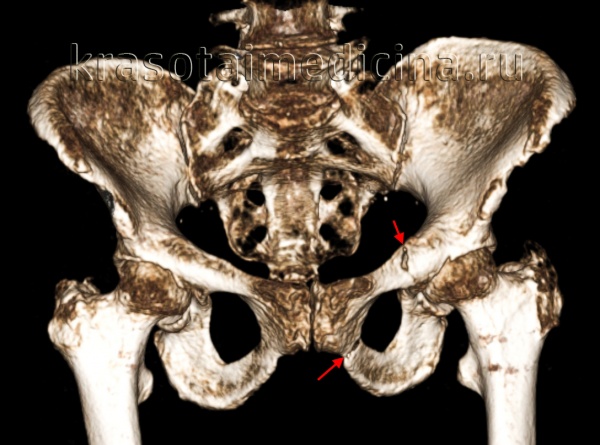

Класс А: I тип отрывные переломы костей таза. Эти переломы характерны для молодых спортсменов и связаны с сильным сокращением мышц в области, где располагаются еще не закрывшиеся апофизы. Ниже см. возраст закрытия апофизов.

Кроме того, у молодых спортсменов возможен вызванный приводящими мышцами отрыв лонного симфиза. После перелома может наблюдаться избыточное мозолеобразование, которое иногда принимают за новообразование.

Каждому типу отрывного перелома сопутствует различный механизм повреждения. Класс А: тип IA. Эти переломы обычно встречаются у молодых спринтеров и являются следствием сильного сокращения портняжной мышцы. Смещение, как правило, незначительное и ограничивается прикрепленной к этой кости паховой связкой и широкой фасцией бедра.

Класс А: тип IБ. Эти переломы встречаются реже переломов типа IA и являются следствием сильного сокращения прямой мышцы живота, например при сильном ударе по мячу при игре в футбол. Класс А: тип IB. Эти повреждения, как правило, встречаются у спортсменов, энергично пользующихся мышцами этой группы, таких как бегуны с барьером или прыгуны с шестом. Крестцово-бугорная связка препятствует смещению седалищного бугра.